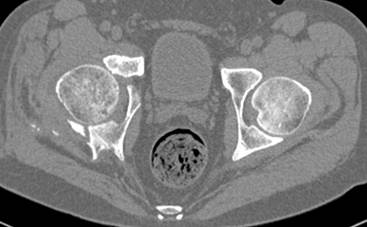

итак, второй вариант: высокий двухколонный с вовлечением КПС... Ни одно из основных повреждений не репонировано, кроме задней стенки. Скорее всего попытка реконструкции вертлуги сейчас будет очень травматичной и не очень эфективной, т.е. вероятный риск более значим, чем ожидаемая польза... Лучше подождать, и потом сразу эндопротез

подождать сколько, чего? такая дыра в задней колонне не закроется никогда.

потом эндопротез какой? в такой ситуации приходит на ум Burch-Schneider cage, в 35 лет, дальше что делать?